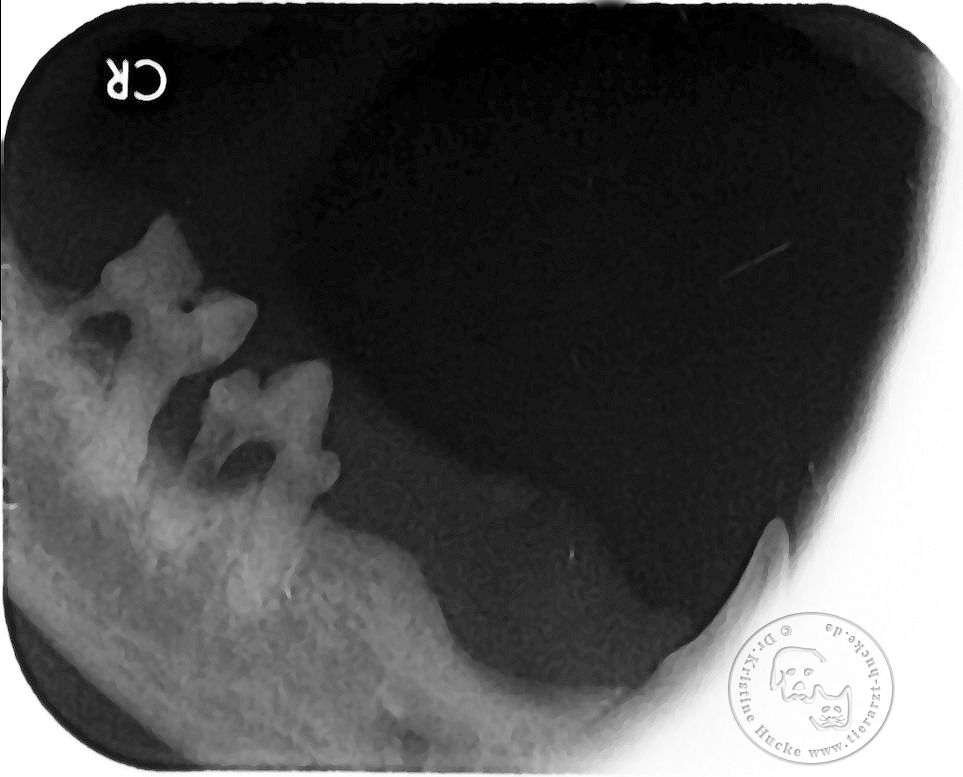

Hier noch ein Beispiel aus dieser Woche,

ein Beispiel wie wichtig das dentale Röntgen für uns ist!

Zunächst sieht alles nach einer normalen Zahnsanierung einer zehnjährigen Katze aus, der bereits einige Zähne im Maul fehlen,

bei einer allgemeinen Untersuchung fiel uns nur eine kleine gerötete Stelle am Zahnfleisch am Molar 1 auf.

Nach der Zahnreinigung mit Ultraschall und der Sondierung der einzelnen Zähne war auch weiterhin nur ein Zahn auffällig, doch dann kam das routinemässige Dentalröntgen!